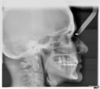

Les radios avant traitement